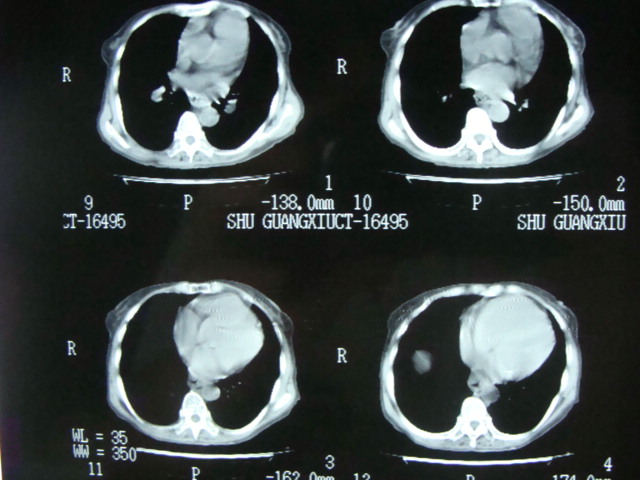

以下是引用老爱克斯新网客在2008-6-2 6:38:00的发言:[br]ct表现是肺动脉根部明显扩张,右心室增大,左房左室及右房都不大,因此可以除外风心。高血压心脏病。冠心病。定位片基本可以除外肺心病,(心肌病。心包积液更不可能)因此除外了后天性获得性心脏病。其表现也可以除外室缺。房缺。动脉导管未闭等常见的先心病。如果是原发性肺动脉高压除肺动脉根部扩张外双侧肺动脉尤其是右下肺动脉干应该也有扩张。因此我认为最大的可能是肺动脉瓣狭窄伴有窄后扩张,建议做一下彩超就知道了。期待结果。